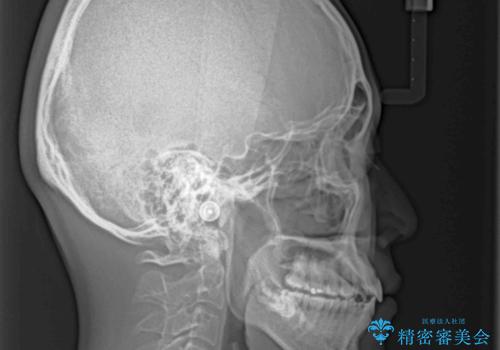

- 全体的なデコボコと、前歯の前に出ている感じを気にして来院された患者様です。

患者様と相談の上、非抜歯にてインビザラインを用いて矯正治療を行うこととし、IPR(歯と歯の間)並びに歯列全体の後方移動により口元の突出感の改善することとしました。

お仕事が忙しい方で、装着時間が不足したり、定期的な通院ができなかったりと、自己管理が重要なインビザラインによる矯正治療が長期化する要因が重なり、5年ほどの期間を要しました。